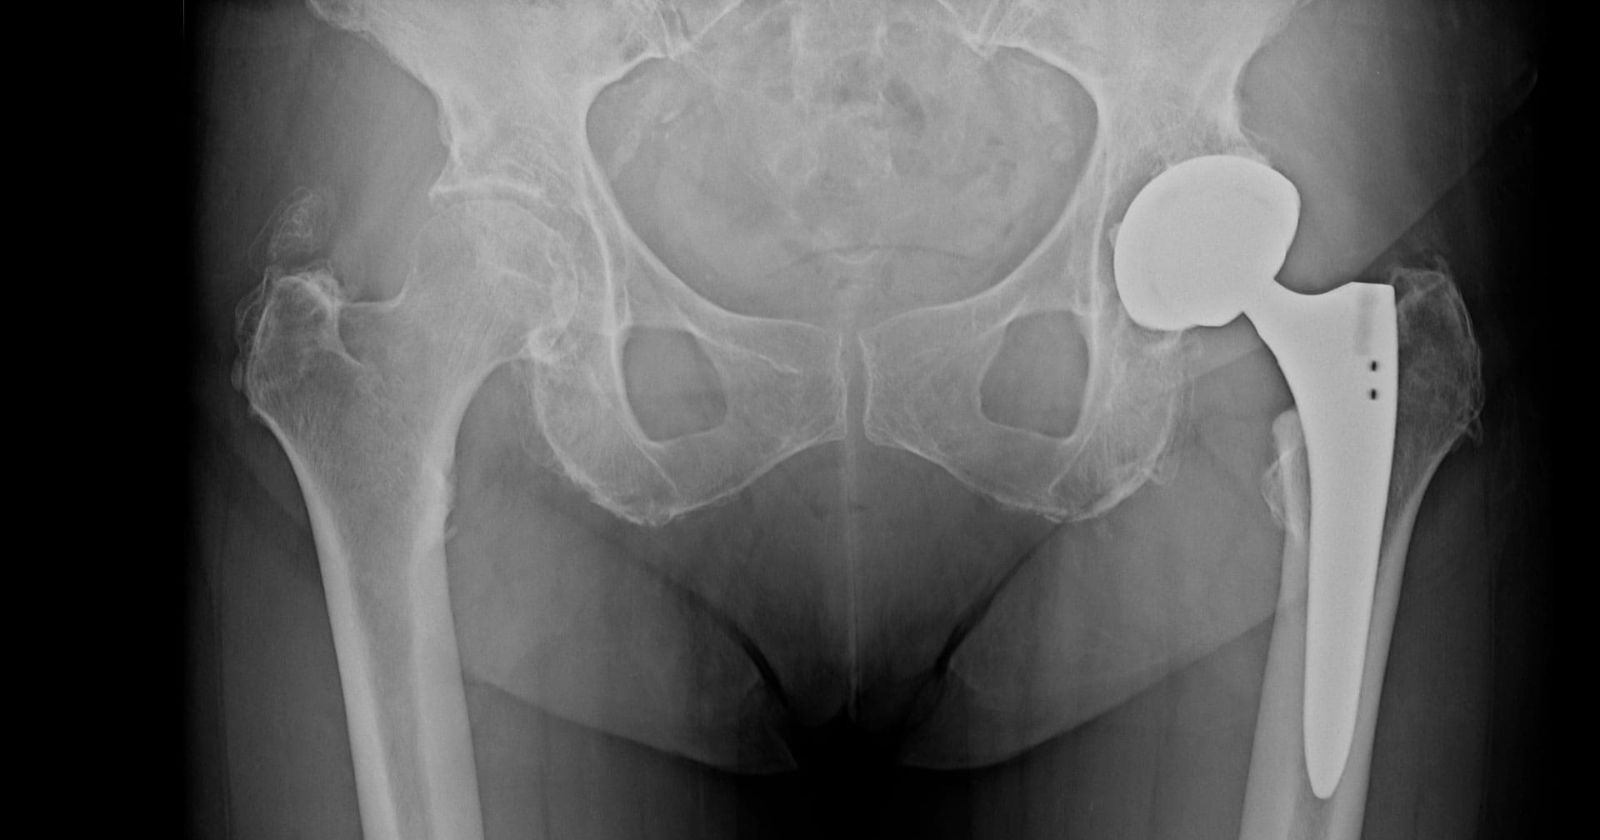

La coxartrosi può dipendere da molteplici fattori: sedentarietà, sovraccarico dovuto a sport o lavoro fisicamente impegnativi, predisposizione genetica, traumi pregressi, disallineamento degli arti inferiori e obesità. Una diagnosi basata su radiografia o risonanza magnetica permette di definire lo stadio della malattia e impostare il trattamento più adeguato. Nelle fasi iniziali si può intervenire con fisioterapia mirata, riposo, farmaci antidolorifici e infiltrazioni ecoguidate. In casi più delicati, invece, il chirurgo può proporre terapie biologiche con cellule staminali mesenchimali, utili per ridurre dolore e infiammazione. Quando la degenerazione è avanzata e la qualità di vita compromessa, infine, l'opzione più efficace rimane la protesi d'anca, disponibile in diverse soluzioni, comprese tecniche mini-invasive come la “bikini incision" o protesi di rivestimento pensate per pazienti giovani e sportivi.